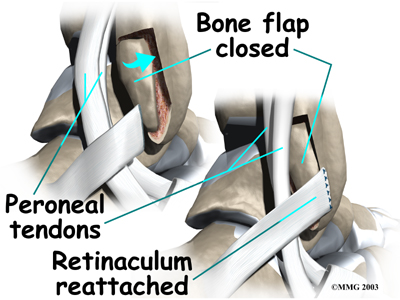

Groove Reconstruction

Groove reconstruction is done to deepen the groove so the peroneals stay in place behind the bottom tip of the fibula. In this procedure, the surgeon first makes an along the back and lower edge of the fibula bone.

The surgeon cuts a small flap in the bone near the bottom corner of the fibula. The surgeon then carefully folds the flap back, like a hinge. With the hinge held open, the doctor scoops out a small amount of bone under the flap to .

The surgeon on its hinge and tamps it in place. A screw may be used to hold the flap down.

Next, the tendons are returned to their location behind the tip of the fibula. Repair of the retinaculum may also be required with this procedure (see above). The skin is closed and sutured.